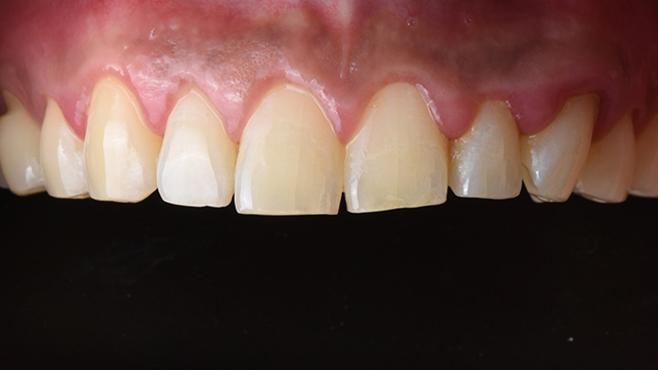

맞는 건 괜찮은데… 충치는 못 참겠습니다|20대 격투기 선수 치과 방문기

2026.02.06